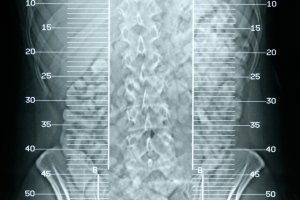

Belirtilerin genellikle menopoz sonrası yapılan muayenelerde ortaya çıktığını söyleyen Şıldır, "İlk belirtiler olarak vücutta yaygın ağrılar görülüyor. Hasta bunun pek farkında olmuyor. Bir yeri kırıldığında bunu fark ediyor. Kırık sonrası yapılan kemik ölçümünde tespit ediliyor. Herkes bunu yaptırabilir. Ayrıca menopozdan sonra kadınlar kontrole geldiğinde kemik ölçümü yapılıyor. Bu ölçüm esnasında vücutta kemik erimesi tespit ediliyor." dedi. Kırk Yaşına kadar herkesin bir kez kemik dansitometri (kemik ölçümü) yaptırmasında fayda vardır.